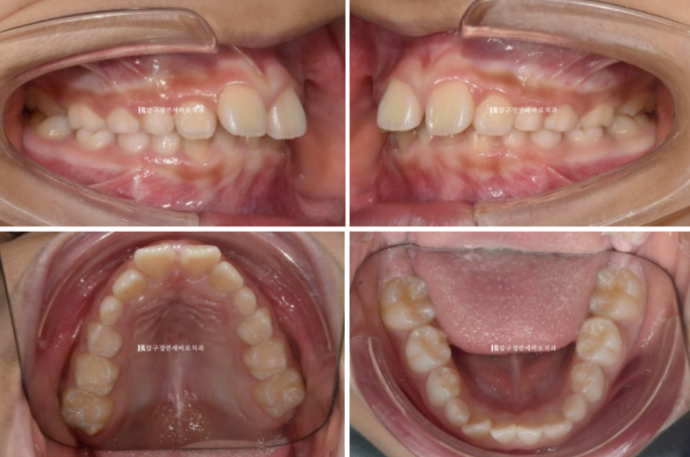

23.09

좁았던 입천장 악궁이 넓어졌고 앞니 배열이 가지런해졌습니다.

클린체크 치료계획상 25단계 장치에서 기대되는 치열이고 치료경과가 좋아서 실제 입안 상태도 비슷합니다.

이제 본격적으로 무턱에 대한 성장교정을 시작할 단계입니다.

실제로 입안에서는 이렇게 구현이 됩니다.

아래턱을 내밀어서 물지 않으면 윙끼리 간섭때문에 입이 다물리지 않습니다.

앞에서 보면 이런 모습입니다.